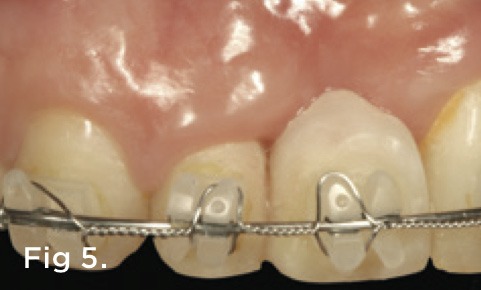

A 38-year-old Caucasian female patient presented with a high smile line and loss of the papilla between tooth No. 7 and edentulous adjacent site No. 8 (Figure 1). Understandably, the patient was unhappy and embarrassed about her esthetic condition. Her dental history revealed tooth replacement of No. 8 with an implant that eventually failed. The site had been previously bone grafted upon implant removal. She was given a composite pontic No. 8 bonded to a tooth No. 7 composite veneer as a transitional restoration. The implant was positioned too close to the proximal surface of tooth No. 7, which stripped the periodontal attachment of the root and ultimately caused loss of the papilla (Figure 2). As previously outlined, the treatment sequence would be to first provide a provisional restorative solution to evaluate the projected outcomes and assess if the patient was willing to undergo orthodontic therapy. In this situation, a full-coverage crown No. 7 with a cantilevered pontic No. 8, with artificial acrylic gingiva to replace the lost papilla on the mesial aspect of tooth No. 7 was used as a transitional temporary prosthesis (Figure 3). In addition, a composite resin restoration was placed on the mesial aspect of tooth No. 9 to restore its individual tooth proportion and shape. The patient’s esthetic outcome could now be evaluated with restorative correction alone; it was therefore mutually determined that the correction of her deformity would best be served with additional orthodontic forced eruption therapy. A fixed orthodontic appliance (brackets) was bonded to the teeth and temporary prosthesis. The level of the interproximal pink acrylic was used as a therapeutic guide for the amount of forced eruption required as well as the alignment of the mesial papilla of No. 7 to that of the adjacent papillae height (Figure 4). Floss was used to elevate the amount of vertical movement achieved relative to the adjacent papilla tooth No. 9. Eventually, all the artificial pink acrylic was removed. (Note that the distal papilla on tooth No. 7 also comes more incisal—in fact, it is slightly excessive at the endpoint of treatment [Figure 5]). However, the distal papilla and midfacial tissues of tooth No. 7 can be reshaped through clinical crown lengthening toward the end of treatment prior to definitive restoration, thereby restoring the proper papilla height-to-tooth ratio of 40%. After stabilization of tooth No. 7 for a minimum of 6 months post-orthodontics, an implant was placed in site No. 8. A papilla-sparing incision design was used for flap elevation (Figure 6), bone allograft was used to further augment the facial aspect of the ridge simultaneously with implant placement (Figure 7), and a resorbable membrane was used for guided bone regeneration.

Fig 4. A fixed orthodontic appliance was placed and the interproximal tissues were moved to be more incisal, as was the midfacial on tooth No. 7, which is negotiated through crown lengthening after tooth movement was complete. The pink acrylic was removed as the tooth relocated.

Figure 4

Fig 5. After completed forced eruption, tooth No. 7 was stabilized for 6 months. All the pink acrylic was eventually removed and the mesial papilla was now coincident with that of tooth No. 9.

Figure 5